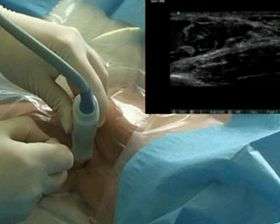

![]() Video of a brachial plexus block, using a portable ultrasound scanning device for localization of the nerves of the brachial plexus | |

Brachial plexus block is typically performed by an anesthesiologist. To achieve an optimal block, the tip of the needle should be close to the nerves of the plexus during the injection of local anesthetic solution. Commonly employed techniques for obtaining such a needle position include transarterial, elicitation of a paresthesia, and use of a peripheral nerve stimulator or a portable ultrasound scanning device.[3] If the needle is close to or contacts a nerve, the subject may experience a paresthesia (a sudden tingling sensation, often described as feeling like "pins and needles" or like an electric shock) in the arm, hand, or fingers. Injection close to the point of elicitation of such a paresthesia may result in a good block.[3] A peripheral nerve stimulator connected to an appropriate needle allows emission of electric current from the needle tip. When the needle tip is close to or contacts a motor nerve, characteristic contraction of the innervated muscle may be elicited.[3] Modern portable ultrasound devices allow the user to visualize internal anatomy, including the nerves to be blocked, neighboring anatomic structures and the needle as it approaches the nerves. Observation of local anesthetic surrounding the nerves during ultrasound-guided injection is predictive of a successful block.[4] Appropriate block per site-specific procedure are listed in the following table:[5]